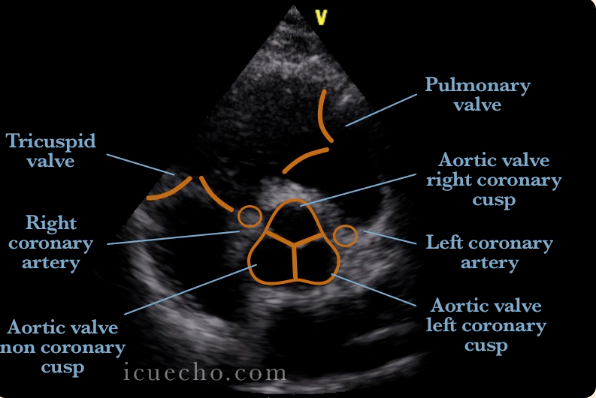

The arrow (gray one) in this image is pointing to the:

A

Left main coronary artery

*the image demonstrates the left coronary artery originating from the left coronary cusp

Q

In this image, the arrow is pointing to the:

What is the arrow pointing to this image?

right coronary cusp